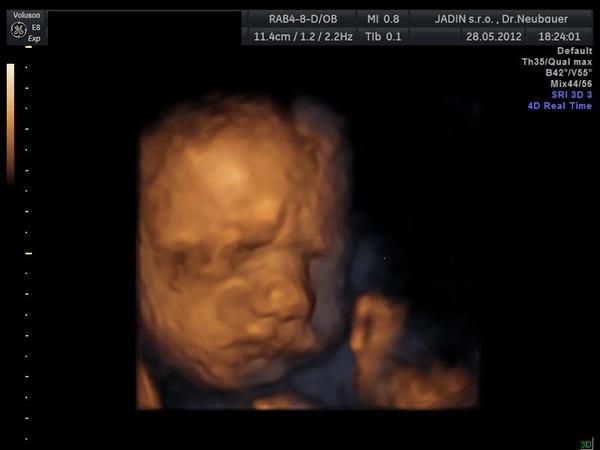

takze doma z USG 🙂 vsetko OK mala ma 1 490g 🙂 joooj ako sa vrtela 🙂 hned pridam foto 😉